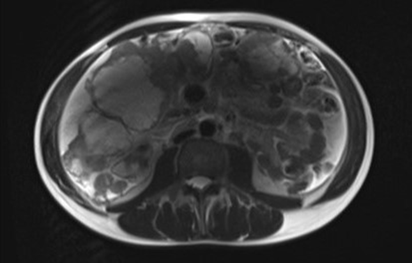

Magnetic resonance imaging (mri) confirmed the ct findings, displaying a mass

with restricted diffusion and central necrosis and established the differential

diagnosis of a primary peritoneal lesion, sarcoma or stromal tumour (figure

2). Ultrasound-guided biopsy and histological examination established the

Figure 2: abdominal

mri: the mass has high intensity on t2-weighted images